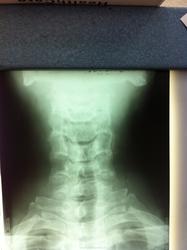

Что это может быть? позади остистого отростка С5, в мягких тканях...

Было уже. Кость выйной связки. http://www.radiomed.ru/cases/sheinyi-otdel-pozvonochnika-sluchainaya-nakhodka

обызвествление выйной связки.

Соглашусь с 1 постом, по плотности- это конечно кость, а не обызвествление ( связки),( метаплазию мягких тканей в костную, как у Рейнберга, никто не отменял).

то-бишь не кальцификация ,а оссификация выйной связки.Есть прекрасная монография  Дьяченко В.А. "Рентгенодиагностика обызвествлений и гетерогенных окостенений". Медгиз, 1960 г.,очень рекомендую